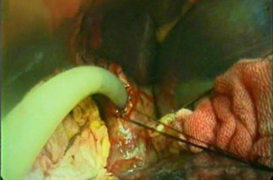

腹腔镜手术是胆囊切除的主流方法,术后恢复快,手术本身对人体影响不大。胆囊的主要功能是浓缩和储存胆汁,所以胆囊切除术后短期内需低脂饮食,一般3个月后胆管会代偿性扩张起到部分胆囊的作用,那时可基本正常饮食,对生活没有明显影响。

与传统开腹手术相比,腹腔镜胆囊切除术有哪些优势?

1.伤口小 腹部微小切口,0.5cm至1cm,基本不留疤痕。

2.疼痛轻 患者疼痛感小,手术采取静脉麻醉,患者在睡眠的状态下完成手术。一般病人术后不再需要止痛药物。

3.术中视野清楚 可以同时对其它脏器进行观察,同时兼有诊断和治疗作用;操作者双手不进入腹腔,对其它脏器干扰较少;

4.损伤轻、恢复快 大大减少了对脏器的损伤和对脏器功能的干扰,使术后恢复时间缩短。

5.住院时间短 一般情况下手术后6-8小时可下床, 12-24小时肛门排气即可进食,3-5天出院,一周后基本恢复,费用相对降低。

6.出血少 术中几乎不出血,微创手术视野比较清楚,血管处理会更精细,加上采用超声刀等先进手术器械,更能减少术中出血量。

我科对胆囊疾病的优势

1.对各种急、慢性胆囊炎,胆囊结石等患者,全部采用腹腔镜下胆囊切除术,手术切口小,出血少,恢复快,费用低。